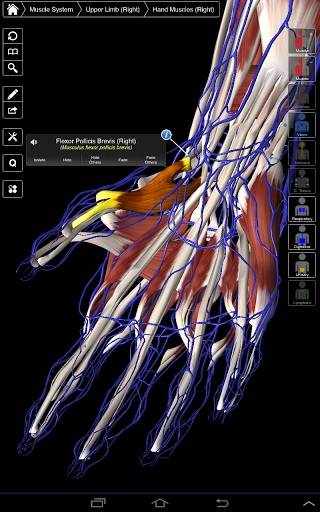

Essential Anatomy 3 represents the latest in groundbreaking 3D technology and innovative design. A cutting edge 3D graphics engine, custom built by 3D4Medical from the ground up, powers a highly-detailed anatomical model and delivers outstanding quality graphics that no other competitor can achieve.

The app represents a unique approach to learning general anatomy. The graphics are unparalleled and make learning, through the use of informative content and innovative features, a rich and engaging experience.

Essential Anatomy 3 is responsive, visually stunning and effortless. The app is fully 3D, meaning that you can view any anatomic structure in isolation, as well as from any angle.

Clever functionality found within the app allows the user to strip away layers of muscle via the ‘scalpel’ tool. This app provides users with the ability to turn on/off systems without the need to deselect individual structures or muddle through a multitude of predefined regional tabs, like other apps.

---- Over 4,000 highly detailed anatomical structures

---- Latin nomenclature for each anatomical structure